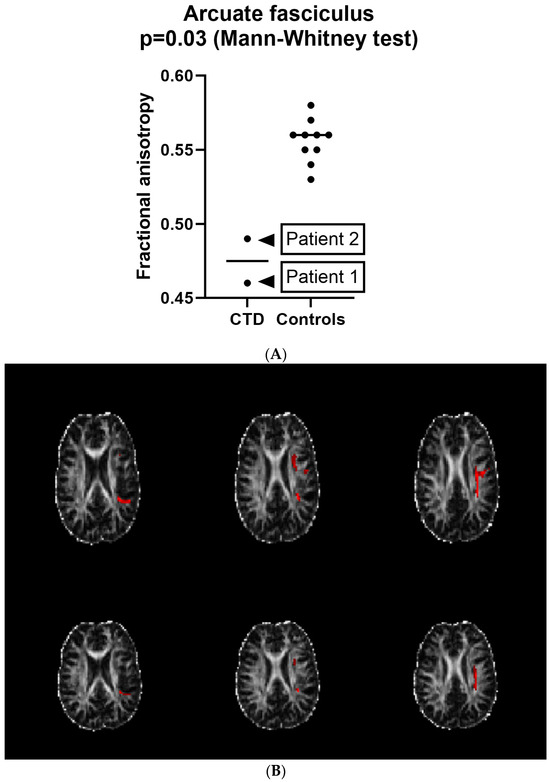

Selective Alteration of the Left Arcuate Fasciculus in Two Patients Affected by Creatine Transporter Deficiency

by Maurizio Balestrino, Enrico Adriano, Paolo Alessandro Alì and Matteo Pardini

Brain Sci. 2024, 14(4), 337; https://doi.org/10.3390/brainsci14040337 - 30 Mar 2024

(1) Background: In hereditary creatine transporter deficiency (CTD), there is an absence of creatine in the brain and neurological symptoms are present, including severe language impairment. However, the pathological changes caused by creatine deficiency that generate neuropsychological symptoms have been poorly studied. (2) [...] Read more.

(1) Background: In hereditary creatine transporter deficiency (CTD), there is an absence of creatine in the brain and neurological symptoms are present, including severe language impairment. However, the pathological changes caused by creatine deficiency that generate neuropsychological symptoms have been poorly studied. (2) Aims: To investigate if the language impairment in CTD is underpinned by possible pathological changes. (3) Methods: We used MRI tractography to investigate the trophism of the left arcuate fasciculus, a white matter bundle connecting Wernicke’s and Broca’s language areas that is specifically relevant for language establishment and maintenance, in two patients (28 and 18 y.o.). (4) Results: The T1 and T2 MRI imaging results were unremarkable, but the left arcuate fasciculus showed a marked decrease in mean fractional anisotropy (FA) compared to healthy controls. In contrast, the FA values in the corticospinal tract were similar to those of healthy controls. Although white matter atrophy has been reported in CTD, this is the first report to show a selective abnormality of the language-relevant arcuate fasciculus, suggesting a possible region-specific impact of creatine deficiency. Full article